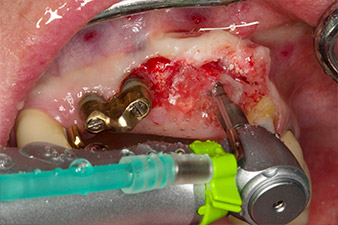

Нарязване с винт с обратен наконечник WS-75 L

Фиг. 3: Нарязване с винт с обратен наконечник WS-75 L със съотношение 20:1 (програма P4). Високият въртящ момент на Implantmed, хексагоновата система на цангата за надеждно предаване на мощноста и автоматичното обръщане на посоката на въртене, когато съпротивлението стане твърде голямо, са особено полезни в този случай.